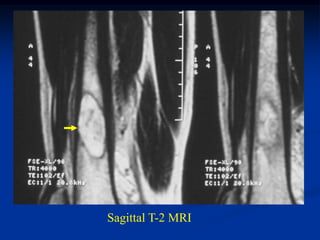

Case #1095

58 year female with

adamantinoma tibia

Sagittal T-1 MRI

Sagittal T-2 MRI